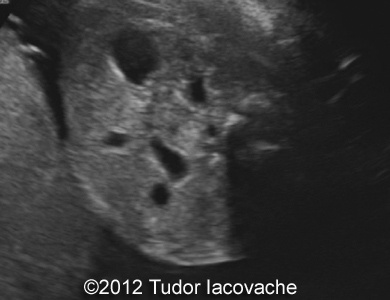

At 22 weeks the scan was suggestive of duodenal stenosis, with "double bubble" sign , no other anomalies, normal amniotic fluid. Karyotype was performed and was normal 46XX. The pregnancy continued with no problems and normal amniotic fluid.

The images and video clip are of the 22-week scan and shows the typical double bubble with dilation of the proximal duodenum and communication with the stomach.

Image 1-4: